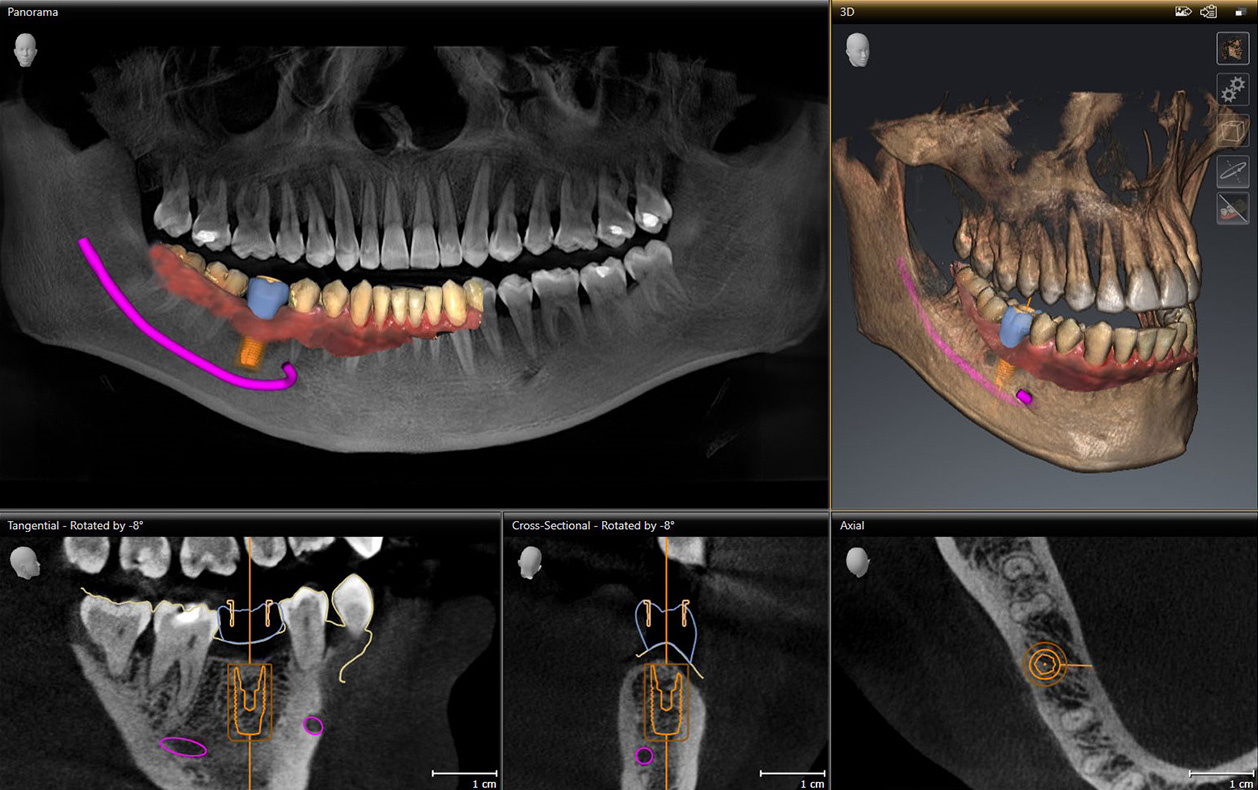

Das 3D-Implantat und die 3D-Implantologie in Bonn –

Mit moderne Implantat-Diagnostik und 3D-Implantatplanung sicher implantieren

Quelle: Dentsply Sirona

Die moderne, minimalinvasive Chirurgie erlaubt es heutzutage, Zahnimplantate schmerzarm, präzise und gewebeschonend mithilfe einer Bohrschablone einzusetzen, um Zahnersatz auf Implantaten sicher und stabil zu verankern und die Funktionalität und Ästhetik der Zähne langfristig wiederherzustellen.

In der Implantologie hat die minimalinvasive Chirurgie auch in unserer Zahnarztpraxis für Zahnimplantate in Bonn ihren festen Sitz eingenommen. Dabei ermöglicht es die moderne digitale Röntgentechnologie, mittels spezieller Simulationssoftware Zahnimplantate dreidimensional im Kiefer zu planen.

Mithilfe der digitalen Volumentomographie (DVT) sind wir dazu in der Lage, eine exakte 3D-Ansicht der knöchernen Strukturen zu erzeugen, sodass eine genaue Diagnose und Behandlungsplanung des chirurgischen Eingriffes möglich wird.

Unter Berücksichtigung des vorhandenen Knochenangebotes und Schonung anatomischer Strukturen wie Kiefer- und Nasenhöhle, Nerven sowie benachbarter Zähne werden die

Implantate im Vorfeld mittels Planungssoftware am Bildschirm in 3D digital geplant und so der Implantattyp, die Anzahl der Implantate und die bestmögliche Implantatposition im Kiefer für eine optimale spätere prothetische Versorgung gewählt.

Anhand der 3D-Röntgendiagnostik und der computergestützten digitalen 3D-Implantatplanung wird eine spezielle individuelle Bohrschablone für die spätere Implantation angefertigt, die so eine geführte, navigierte und sichere Implantation ermöglicht (navigierte Implantation oder Guided Surgery). Für Patienten erhöht der Einsatz einer Bohrschablone nicht nur die Sicherheit des implantologischen Eingriffs immens, sondern er verkürzt zudem die Operationszeit deutlich, was die möglichen Folgen eines chirurgischen Eingriffes wie Schwellung und Schmerzen wesentlich minimiert. Auch ein aufwändiger Knochenaufbau (Knochen-Augmentation) vor der Implantation ist oft nicht mehr notwendig, da der vorhandene Knochen optimal genutzt werden kann, was eine deutliche Zeit- und Kostenersparnis darstellt.

Mit einer Bohrschablone präzise gesetzte Implantate schaffen für die Implantat-Prothetik zudem optimale Voraussetzungen für die Herstellung des implantatgetragenen Zahnersatzes sowie herausragende ästhetische Resultate. Als zertifizierter Zahnarzt für Zahnimplantate in Bonn und langjähriges Mitglied der deutschen Gesellschaft für Implantologie (DGI) berate ich Sie gerne über alle Möglichkeiten, die die moderne digitale Implantologie bietet.